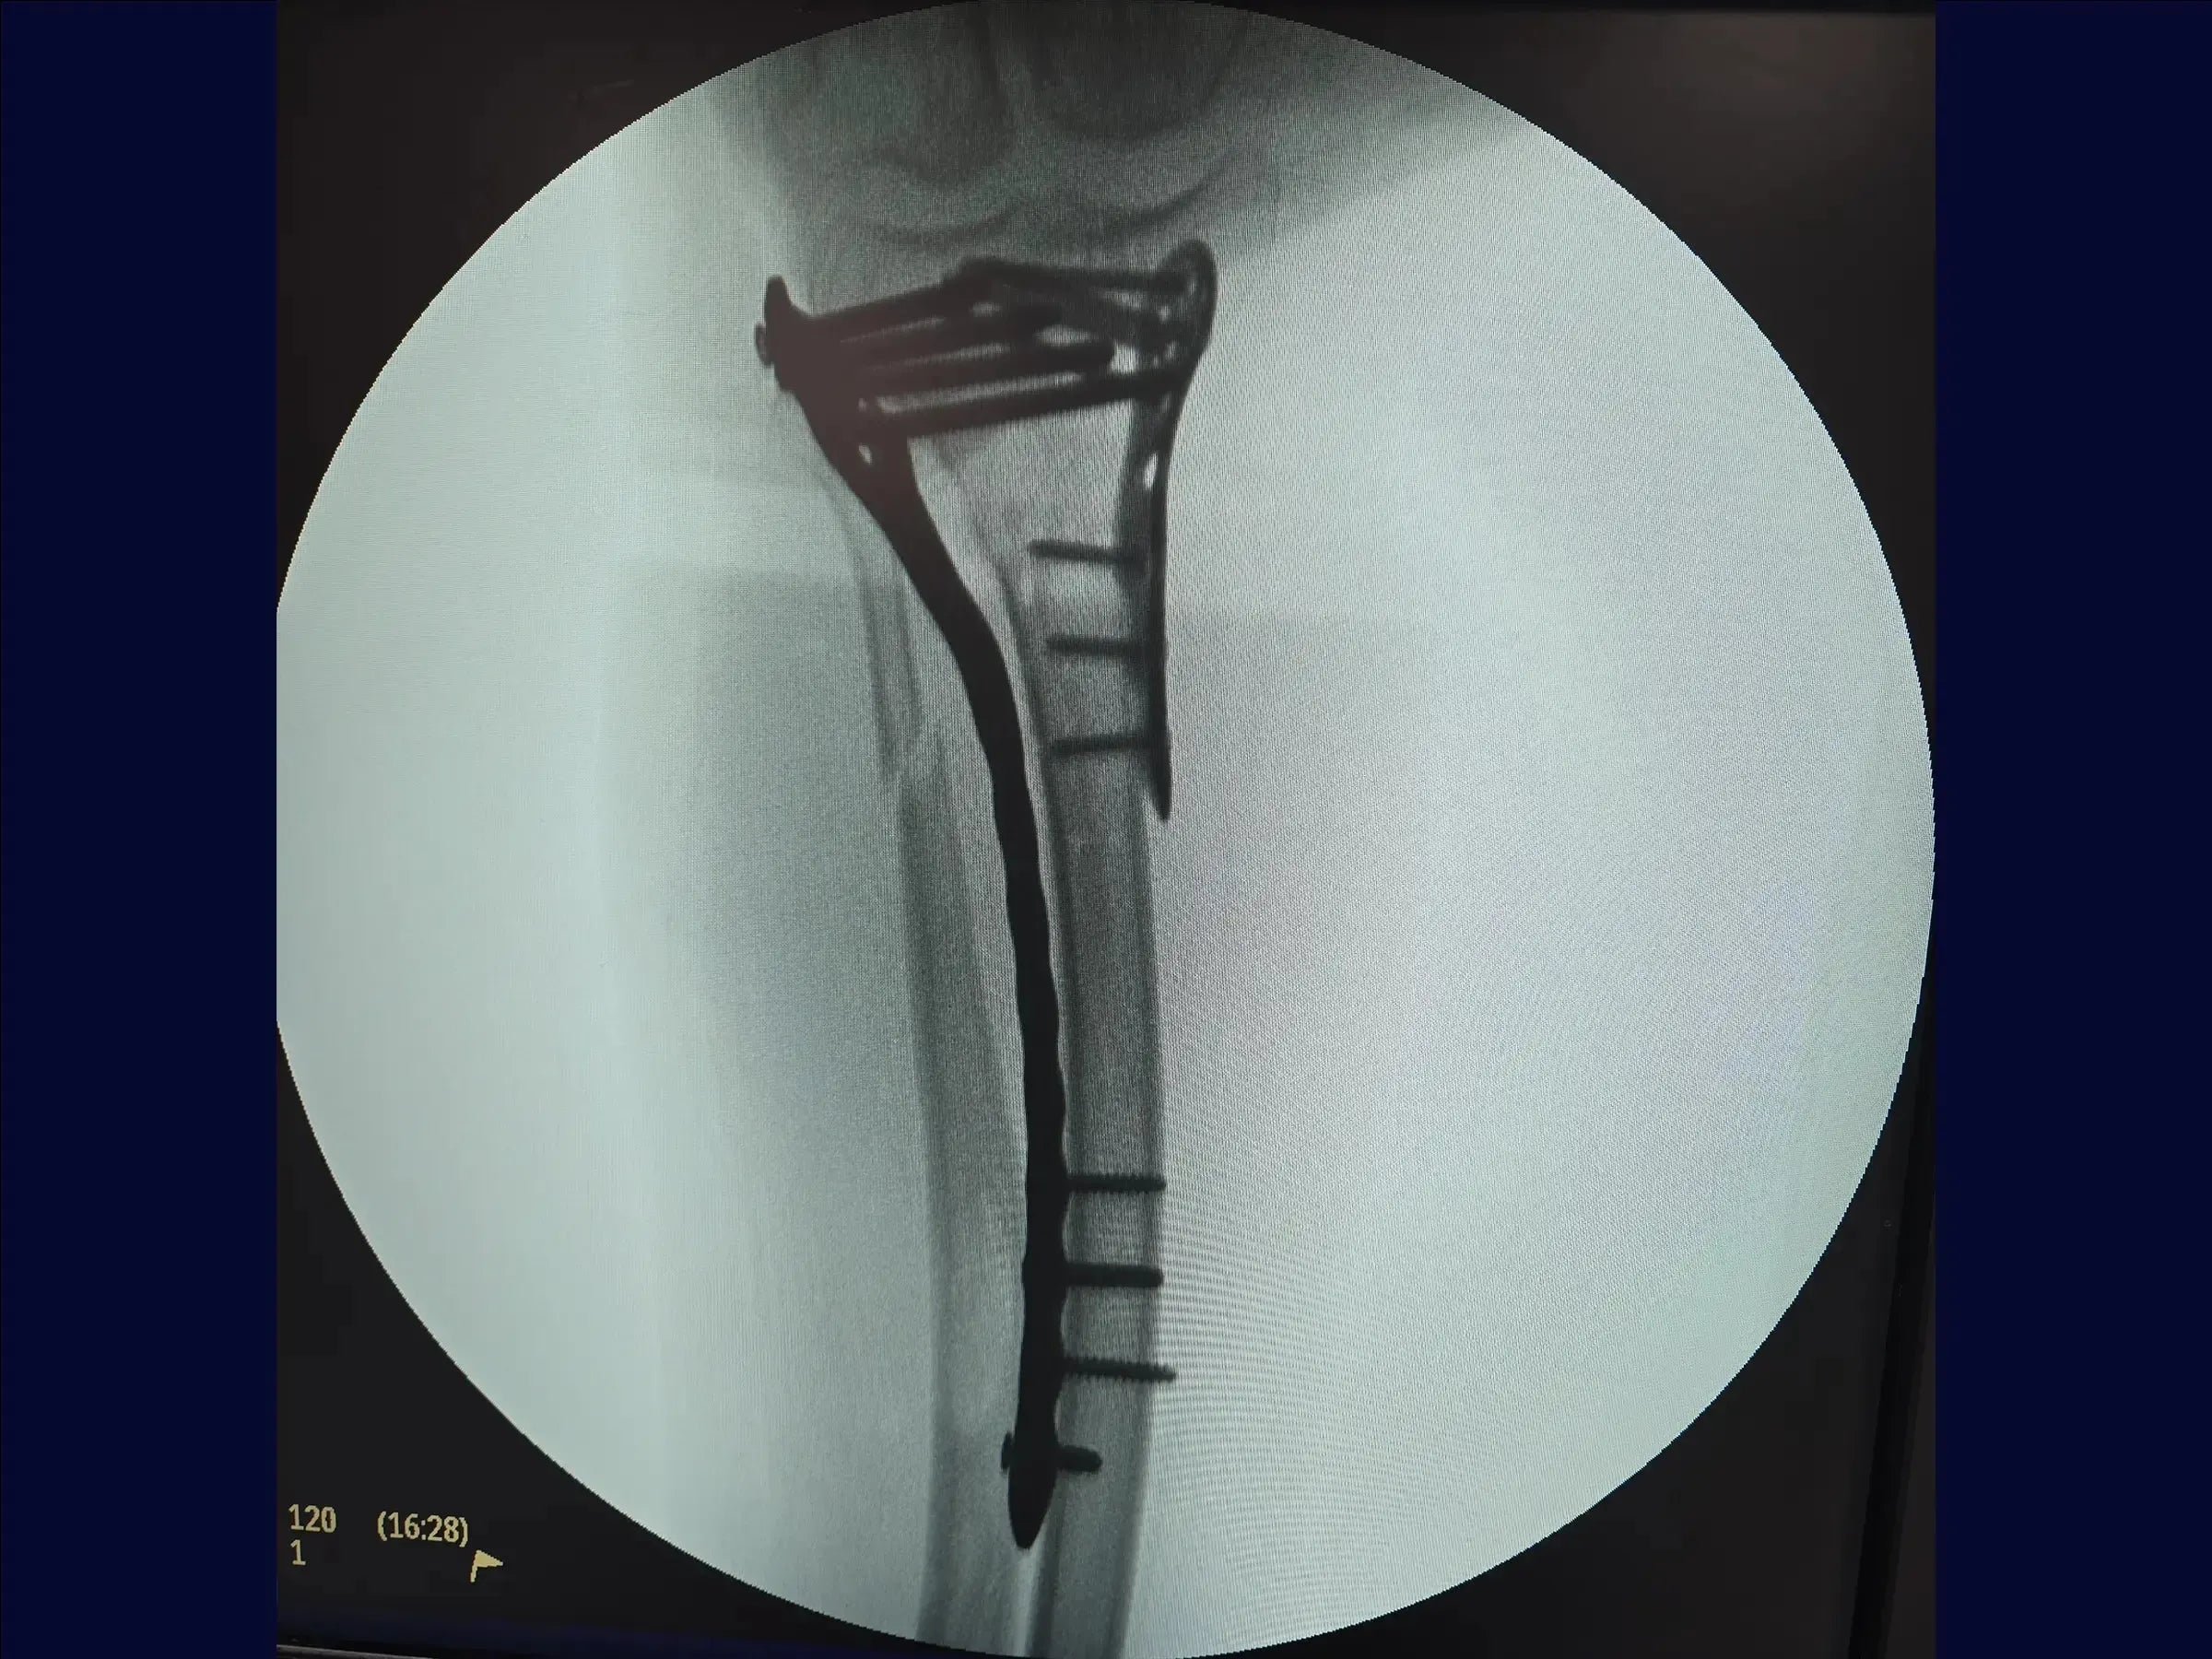

- Anti-shear fixation with anatomical medial plate.

- Anti-Shear Fixation Medial: Anatomical fibula plate with multiple proximal screws for alignment and indirect reduction.

- Stable Fixation with Cortical and Locked Screws: Strategic combination for torque, stability, and load distribution.